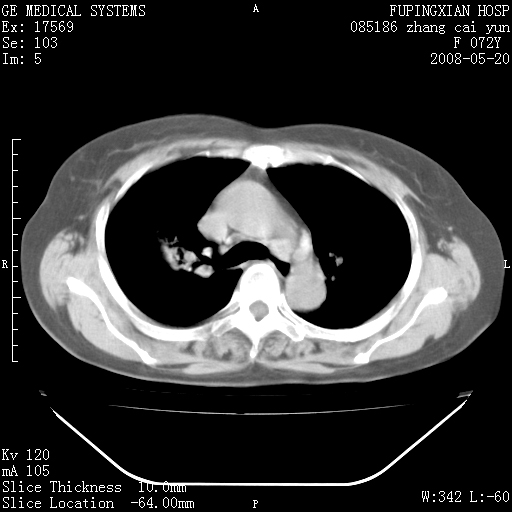

标题: CT13542:发热,咳嗽数日,经抗菌素治疗好转,请大家看排除 [打印本页]

标题: CT13542:发热,咳嗽数日,经抗菌素治疗好转,请大家看排除

上叶支气管略变窄并通畅,内壁光滑。考虑:单纯阻塞性肺炎!

右上叶支气管走行自然,未见明显管壁增厚等征像,另左主支气管起始部可见异常腔道向左侧延展左肺动脉干后方,与左下叶支气管相通,为左下叶支气管变异?

有节段性阻塞性肺炎与不张,近段支气管狭窄,周围散在肿大淋巴结影,以周围型肺癌可能性大,建议纤支镜检查。

右肺上叶实变影,内见支气管充气征,右上叶支气管通畅,肺门区未见软组织密度影,抗炎治疗有效,考虑炎症,建议继续抗炎治疗复查。

右上肺实变,间内有支气管充气征,考虑炎症,建议抗炎后复查